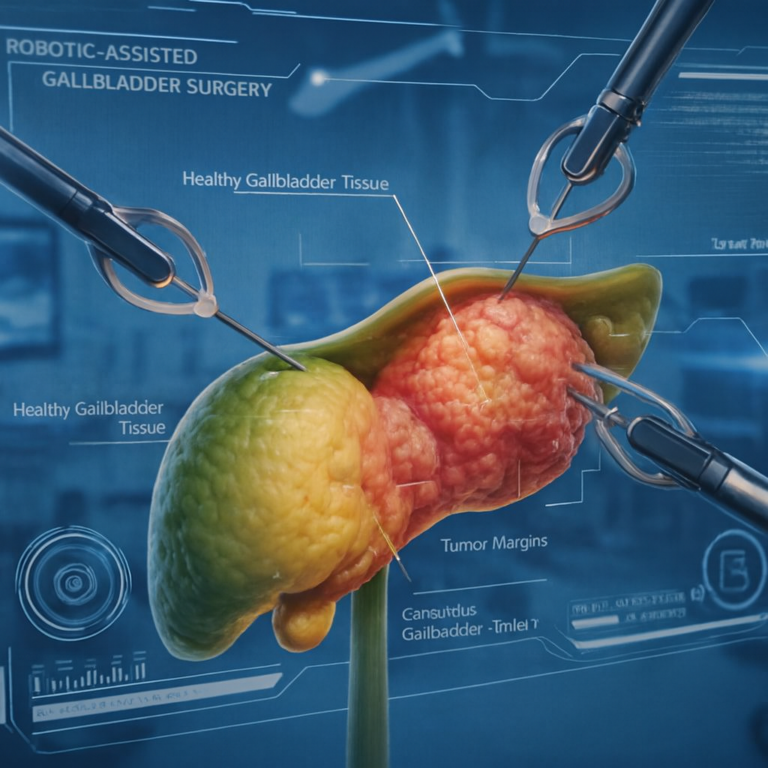

Gallbladder Tumor Treatment In Mira Road The Surprising Fact When it comes to Gallbladder Tumour Treatment in Mira Road, patients often face…

A Gi Oncology Specialist in Mira Road offers expert diagnosis and advanced treatment When it comes to specialized cancer care, finding the…

Introduction Gallbladder cancer surgery in Mira Road, let’s understand. Gallbladder cancer is a rare but aggressive disease that often requires timely surgical…